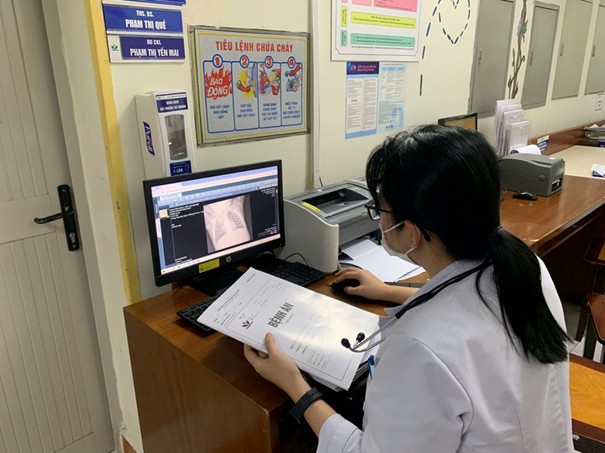

Khi bệnh viện triển khai hồ sơ bệnh án điện tử, bệnh án giấy có còn được sử dụng hay không?

Thứ Hai, ngày 07/07/2025 01:25Ngày 06/6/2025, Bộ trưởng Bộ Y tế đã ban hành Thông tư hướng dẫn triển khai hồ sơ bệnh án điện tử. Thời điểm thông tư có hiệu lực, cơ sở y tế cũng như người bệnh muốn biết bệnh án giấy có còn...